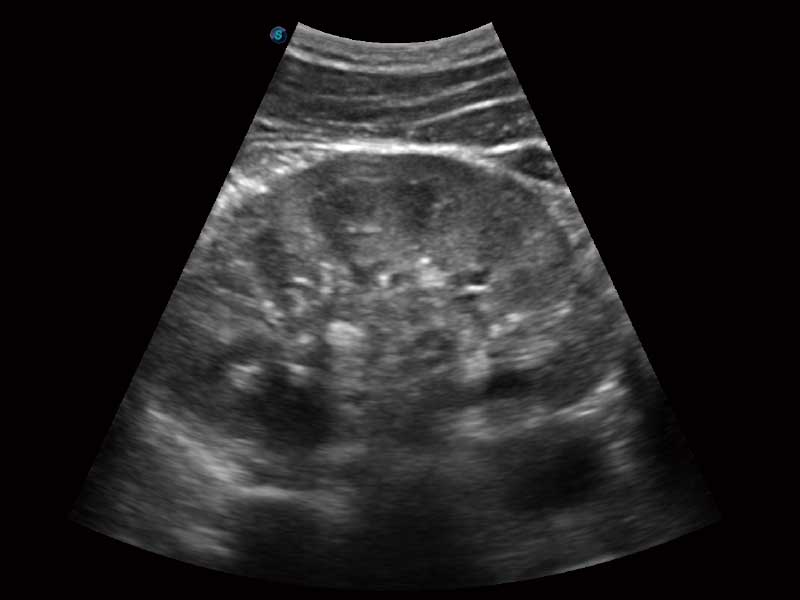

临床图